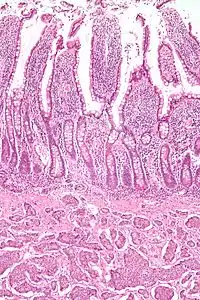

| Micrograph of a neuroendocrine tumor. H&E stain. | |

NETs are often small, yellow or tan masses, often located in the submucosa or more deeply intramurally, and they can be very firm due to an accompanying intense desmoplastic reaction. The overlying mucosa may be either intact or ulcerated. Some GEP-NETs invade deeply to involve the mesentery.[72] Histologically, NETs are an example of "small blue cell tumors," showing uniform cells which have a round to oval stippled nucleus and scant, pink granular cytoplasm. The cells may align variously in islands, glands or sheets. High power examination shows bland cytopathology. Electron microscopy can identify secretory granules. There is usually minimal pleomorphism but less commonly there can be anaplasia, mitotic activity, and necrosis.